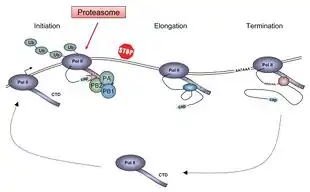

Replication

Viruses can replicate only in living cells.[69] Influenza infection and replication is a multi-step process: First, the virus has to bind to and enter the cell, then deliver its genome to a site where it can produce new copies of viral proteins and RNA, assemble these components into new viral particles, and, last, exit the host cell.[60]

Influenza viruses bind through hemagglutinin onto sialic acid sugars on the surfaces of epithelial cells, typically in the nose, throat, and lungs of mammals, and intestines of birds (Stage 1 in infection figure).[70] After the hemagglutinin is cleaved by a protease, the cell imports the virus by endocytosis.[71]

The intracellular details are still being elucidated. It is known that virions converge to the microtubule organizing center, interact with acidic endosomes and finally enter the target endosomes for genome release.[72]

Once inside the cell, the acidic conditions in the endosome cause two events to happen: First, part of the hemagglutinin protein fuses the viral envelope with the vacuole's membrane, then the M2 ion channel allows protons to move through the viral envelope and acidify the core of the virus, which causes the core to disassemble and release the viral RNA and core proteins.[60] The viral RNA (vRNA) molecules, accessory proteins and RNA-dependent RNA polymerase are then released into the cytoplasm (Stage 2).[73] The M2 ion channel is blocked by amantadine drugs, preventing infection.[74]

These core proteins and vRNA form a complex that is transported into the cell nucleus, where the RNA-dependent RNA polymerase begins transcribing complementary positive-sense vRNA (Steps 3a and b).[75] The vRNA either is exported into the cytoplasm and translated (step 4) or remains in the nucleus. Newly synthesized viral proteins are either secreted through the Golgi apparatus onto the cell surface (in the case of neuraminidase and hemagglutinin, step 5b) or transported back into the nucleus to bind vRNA and form new viral genome particles (step 5a). Other viral proteins have multiple actions in the host cell, including degrading cellular mRNA and using the released nucleotides for vRNA synthesis and also inhibiting translation of host-cell mRNAs.[76]

Negative-sense vRNAs that form the genomes of future viruses, RNA-dependent RNA polymerase, and other viral proteins are assembled into a virion. Hemagglutinin and neuraminidase molecules cluster into a bulge in the cell membrane. The vRNA and viral core proteins leave the nucleus and enter this membrane protrusion (step 6). The mature virus buds off from the cell in a sphere of host phospholipid membrane, acquiring hemagglutinin and neuraminidase with this membrane coat (step 7).[77] As before, the viruses adhere to the cell through hemagglutinin; the mature viruses detach once their neuraminidase has cleaved sialic acid residues from the host cell.[70] After the release of new influenza viruses, the host cell dies.

Because of the absence of RNA proofreading enzymes, the RNA-dependent RNA polymerase that copies the viral genome makes an error roughly every 10 thousand nucleotides, which is the approximate length of the influenza vRNA. Hence, the majority of newly manufactured influenza viruses are mutants; this causes antigenic drift, which is a slow change in the antigens on the viral surface over time.[78] The separation of the genome into eight separate segments of vRNA allows mixing or reassortment of vRNAs if more than one type of influenza virus infects a single cell. The resulting rapid change in viral genetics produces antigenic shifts, which are sudden changes from one antigen to another. These sudden large changes allow the virus to infect new host species and quickly overcome protective immunity.[65] This is important in the emergence of pandemics, as discussed below in the section on epidemiology. Also, when two or more viruses infect a cell, genetic variation may be generated by homologous recombination.[79][80] Homologous recombination can arise during viral genome replication by the RNA polymerase switching from one template to another, a process known as copy choice.[80]